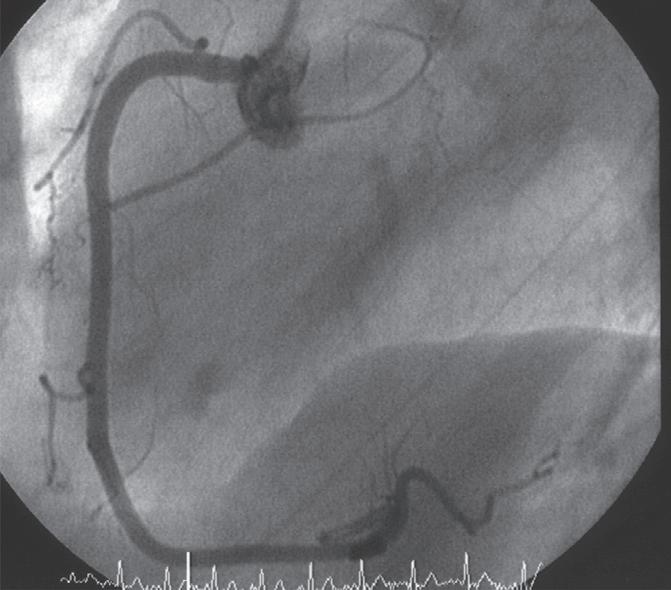

Figura 18.36 – Angiografia da artéria coronária direita. Visualização das diversas colaterais. A. Oblíqua anterior esquerda 45º caudal 15º; B. Oblíqua anterior direita 45º.

Figura 18.37 – Coronariografia da artéria coronária direita (dominante).